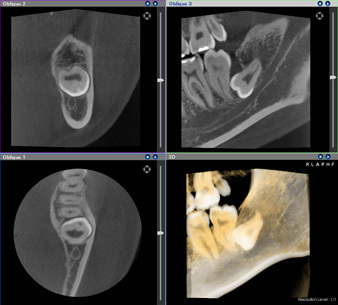

歯科用CT

当院ではCT診断装置を完備しております。

患者様にやさしく、 正確なポジショニングシステムで、高解像度撮影、精緻な画像診断を実現します。